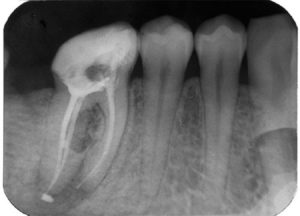

Кариозное поражение бывает разной степени глубины. Иногда сверху оно выглядит небольшим черным пятнышком, разрастаясь в глубь коронки. Поэтому тактика лечения кариеса зависит от того, насколько большую площадь поразило воспаление. Иногда врачу достаточно лишь удалить разрушенные ткани, обработать их специальным препаратом, который обеспечит сцепку с цементом, и запломбировать полость.

Если же кариес проник в недра зуба и, в частности, в пульповую камеру, то приходится удалять нервы и прочищать нервные каналы, обрабатывать их специальным антисептическим препаратом, заполнять композитом, а потом накладывать пломбировочный материал на коронку, либо ставить протез.

В идеале такое лечение должно устранить все очаги воспаления и вернуть зубу его природную функцию. Однако оплошности в лечении, несоблюдение технологии обработки канала или другие факторы могут вызывать повторное воспаление, и тогда пролеченная единица начинает болеть.

3. Перфорация канала или корня

Подготавливая каналы к пломбированию, стоматолог прочищает их специальными тонкими иглами, удаляя остатки нерва, гноя или некротизированных тканей, если таковые имеются. Изгибы проходов иногда такие неожиданные, что врач может случайно проткнуть один из них.

Профессионал, конечно, сразу заметит проблему и тут же закроет отверстие специальным клеем, но вот новичок может не заметить своей оплошности и заложить в перфорированный канал композит.

Это приведет к тому, что часть цемента начнет сквозь отверстие проникать за пределы канала, доставляя человеку дискомфорт.

Крайне неприятным осложнением из-за врачебной ошибки является перфорация твердых тканей зуба (случайное сквозное отверстие). При лечении пульпита или периодонтита, случайная перфорация случается в 3-12% случаев.

В дальнейшем, перфорированная зубная ткань, чаще всего корень зуба, начинает воспаляться и провоцировать различные осложнения.

Выражается процесс сильной болью и дискомфортом, требуется обязательное лечение, иначе высок шанс потери зуба.